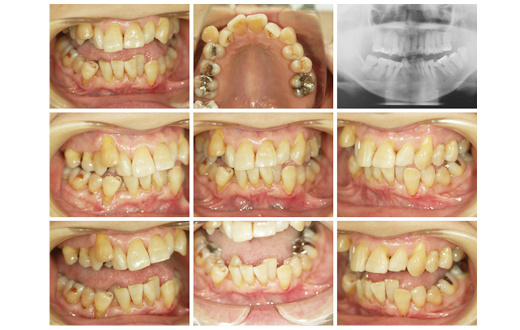

症例 2

女性 46才 1年1カ月